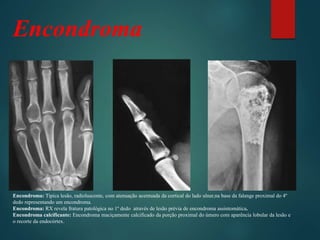

Encondroma: Típica lesão, radioluscente, com atenuação acentuada da cortical do lado ulnar,na base da falange proximal do 4º

dedo representando um encondroma.

Encondroma: RX revela fratura patológica no 1º dedo através de lesão prévia de encondroma assintomática.

Encondroma calcificante: Encondroma maciçamente calcificado da porção proximal do úmero com aparência lobular da lesão e

o recorte da endocórtex.